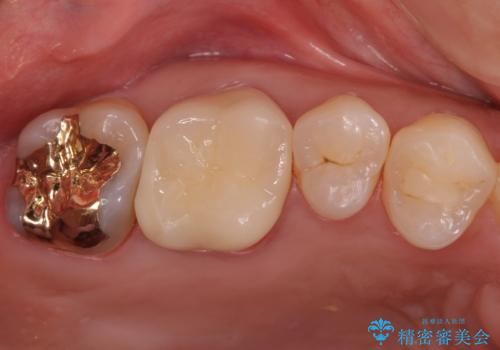

検査で見つかった虫歯 セラミッククラウンでの治療

担当医 岡田康成